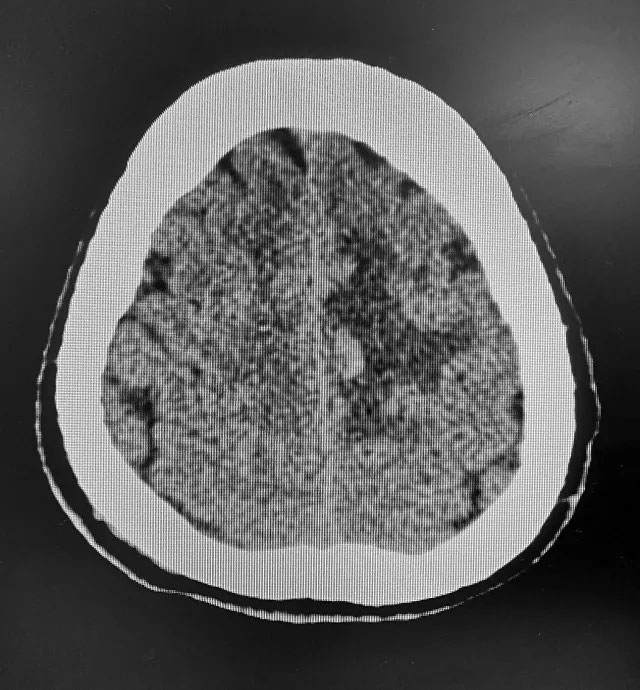

▲患者CT检查影像

64岁患者苏大爷(化名)今年三月份突然无明显诱因出现四肢乏力,不能活动,送当地医院经头颅CT检查诊断为“出血性脑梗死”。经治疗,患者双上肢活动改善,双下肢仍不能活动。家属为求进一步治疗转入上海蓝十字脑科医院。

患者三年前曾患脑溢血,既往高血压病史五年,未长期有效控制,高血压3级,最高血压收缩压224毫米汞柱,舒张压118毫米汞柱。双下肢肌力0级,肌张力高。头颅磁共振显示:左侧额顶叶镰旁亚急性脑梗死伴出血。